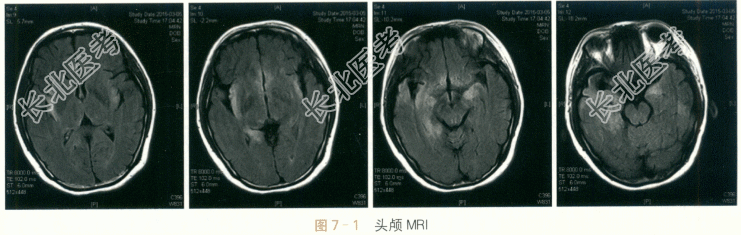

患者,女性,27岁,因“发热、头痛伴精神行为异常半月余”入院。患者半月前无明显诱因下出现发热,体温最高至40℃,同时伴有头痛,以前额部持续性胀痛为主,偶有恶心呕吐,但无咳嗽咳痰、腹痛腹泻。至当地医院门诊以抗生素治疗无好转,并出现胡言乱语、烦躁不安,伴有记忆力减退及定时定向障碍,症状逐渐加重。行腰穿脑脊液中WBC160×10⁶/L,其中M074%;蛋白822mg/L,葡萄糖4.0mmol/L,氯化物122mmol/L;头颅MRI检查提示额叶、颞叶多发病灶伴有增强。予抗病毒及对症支持等治疗,患者无明显好转。1周后复查腰穿,脑脊液WBC165×10⁶/L,M055%;蛋白1008mg/L,葡萄糖2.3mmol/L,氯化物131mmol/L。为进一步诊治收住入院。自患病以来,患者胃纳可,睡眠差,大小便正常,无体重明显下降。既往史:否认肝炎结核史;否认手术外伤史;否认输血史;否认食物、药物过敏史。各系统回顾无特殊。体格检查:(1)内科检查:T37.6℃,P82次/min,BP126mmHg/81mmHg,R16次/min。双肺呼吸音清,心律齐。腹软,肠鸣音正常;肝脾无肿大。(2)神经系统检查:神清呆滞,反应迟钝,查体不合作。对答部分切题,偶有胡言乱语,定时定向差,近时记忆力减退,计算不能。颅神经:双侧瞳孔直径3mm,等大等圆,对光反射良好;眼球各方向运动正常;双侧额纹对称,双侧鼻唇沟对称,口角不偏。双侧软腭上抬可,腭垂不偏,咽反射正常。伸舌居中,无舌肌萎缩及舌肌纤颤。运动系统:四肢肌力检查不配合,四肢可见自主活动,肌张力无增减,肱二头肌反射、肱三头肌反射、桡骨膜反射、膝反射、踝反射均双侧对称(++)。双侧巴彬斯基征、戈登征(-),脑膜刺激征(-)。感觉系统及共济功能:四肢针刺觉、轻触觉、深感觉均对称正常;复合感觉检查不配合;患者共济检查不配合。脑膜刺激征:无颈抵抗;克匿征(-)。血常规:RBC4.12×10¹²/L,WBC13.5×10⁹/L,N85%;FBG4.5mmol/L。肝功能:ALT25IU/L,AST23IU/L,γ-GT27IU/L,AKP80IU/L;TB14lumol/L,DB5.3μmol/L,TP65g/L,ALB40g/L。肾功能:BUN4.4mmol/L,Cr52μmol/L。脑脊液常规:无色,透明度清,潘氏试验(+++),RBC1×10⁶/L,WBC53×10⁶/L,多核细胞17%,M083%。脑脊液生化:糖2.20mmol/L,氯123mmol/L;蛋白773mg/L;同步血糖5.50mmol/L。血清免疫学:抗核抗体、ENA抗体与ANCA均为阴性。结核试验:T-SPOT(-)。肿瘤标志物全套:均为阴性。血清病毒抗体检测:除单纯疱疹病毒Ⅰ型抗体IgG为阳性,巨细胞病毒抗体IgM、巨细胞病毒抗体IgG、单纯疱疹病毒Ⅰ型抗体IgM、单纯疱疹病毒Ⅱ型抗体IgM、单纯疱疹病毒Ⅱ型抗体IgG、EB病毒衣壳抗原抗体IgG、EB病毒衣壳抗原抗体IgM、EB病毒早期抗原抗体IgM与EB病毒抗原抗体IgG均阴性。心电图检查:窦性心律。肺部CT检查:两肺下叶炎症伴两侧少量胸腔积液;左下肺小结节影;肝门区致密影。脑电图检查:双侧见散在2~3Hzδ波、θ波;未见典型痫样放电。头颅MRI检查:双侧岛叶及右侧颞叶见片状长T₁长T₂信号,flair相呈高信号,弥散相无异常(见图7-1)。脑室系统显示可,中线结构无移位。双侧蝶窦黏膜增厚。